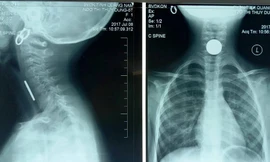

TPO - Bệnh nhi 11 tuổi, nhập viện trong tình trạng nôn ra máu nhiều lần không tự cầm. Kết quả phim chụp cắt lớp vi tính cho thấy ổ giả phình lớn động mạch vị tá tràng.